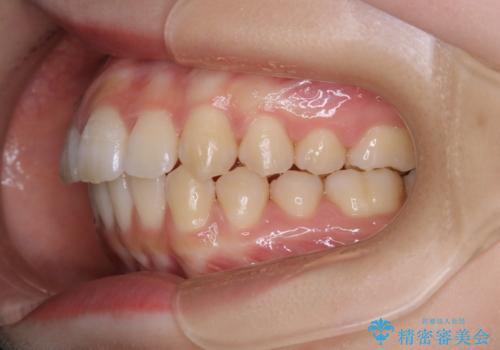

- 前歯の重なりが気になるとご相談にいらした方です。前歯のがたつきは奥歯の噛み合わせのズレが原因となっていたため、インビザラインFULLにて奥歯からしっかり治療していきました。

前歯のがたつきだけを治そうとした場合、噛み合わせは二の次なってしまう事が多く、せっかく綺麗になった歯並びも後戻りしやすくなります。

見た目だけでなく奥歯を移動させて噛み合わせの改善までが行えるのはインビザラインであるからこそです。奥歯の噛み合わせからしっかり機能させることで、長期間にわたって綺麗な歯並びを保ちやすくなります。